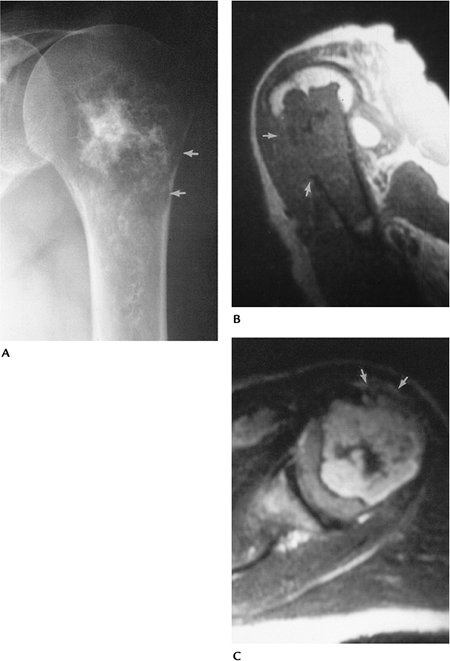

FIGURE 10-32 Central chondrosarcoma. (A) Radiograph of the humerus showing a chondroid lesion with calcifications and endosteal scalloping (arrows). Sagittal T1-weighted (B) and axial T2-weighted (C) images showing cortical destruction with soft tissue mass (arrows) indicating a malignant lesion.